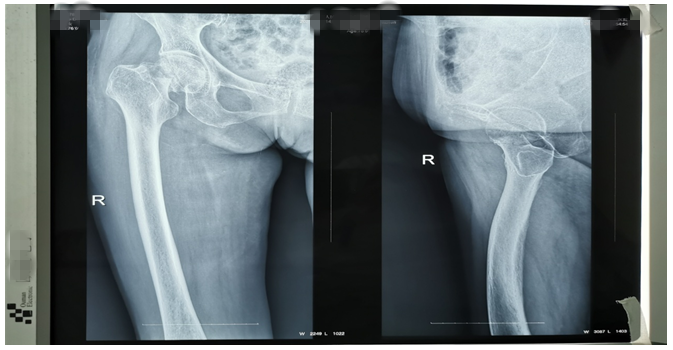

還有一位76歲鄧大媽,外傷致右側(cè)股骨頸骨折。外傷后因疫情鄧大媽一直未就診,在家非常痛苦,因疼痛不能平臥,一直坐位,臀部褥瘡形成,同時被骨折疼痛折磨地夜不能睡、不思飲食。鄧大媽基礎(chǔ)病較多,有高血壓病、腦梗塞、心臟病等病史,因骨折后時間長、錯位明顯,入院后積極治療內(nèi)科疾病,完善各項輔助檢查,在麻醉師及內(nèi)科醫(yī)師協(xié)助下,為鄧大媽成功行右側(cè)髖置換術(shù),手術(shù)順利。術(shù)后鄧大媽的臉上又有了笑容,夜間也能休息好了,術(shù)后第二天就開始下床活動,家屬看到自己的老母親恢復地這么好,非常滿意。(見下圖)

右髖正側(cè)位手術(shù)前后對比圖